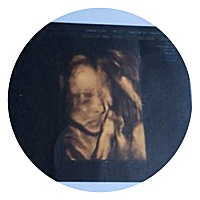

宝宝8天

直到现在还是个迷。。。